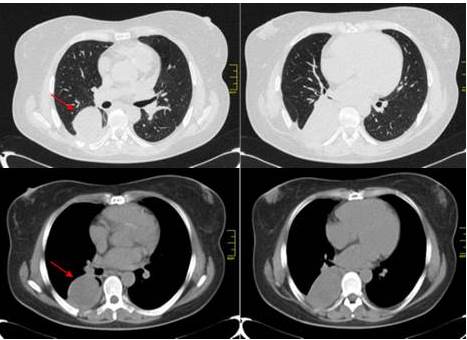

En vista del hallazgo radiológico y clínico, se procede a realizar TAC de tórax para completar el estudio de la paciente, con tomógrafo BRIGHT SPEED® de 16 detectores sin la administración de contraste intravenoso. Se evidencia imagen de masa con márgenes bien definidos con morfología redondeada, que mide entre 9 cm x 7 cm, con valores de atenuación entre 23-43 UH, isodensa homogénea, contornos suaves en contacto con pared torácica y sub-pleural. Ausencia de adenopatías de la cadena mediastinal, supra-carinalis y perihiliar (Figura 6).

El hemangiopericitoma intra-pulmonar es una neoplasia poco frecuente, potencialmente maligna, que se origina a partir de lo pericitos que rodean la membrana basal de los pequeños vasos (capilares y vénulas) dentro del parénquima pulmonar. Tiene un origen mesenquimatoso sobre lo que existen pocas referencias en la bibliografía, con menos de 20 casos publicados (9). Su histogénesis no está clara, existiendo dos teorías sobre su origen: la primera hipótesis propone un origen a partir del mesénquima sub-pleural que se encuentra en continuidad directa con el tejido conectivo de los septos inter-lobulares, mientras que la segunda teoría sugiere que este tumor deriva de los fibroblastos sub-mesoteliales presentes en el parénquima pulmonar normal (10,11,12). La mayoría de casos descritos en la literatura se han diagnosticado en adultos de edad media, de entre 40 y 70 años. El tamaño de las lesiones ha oscilado entre 1 cm y 15 cm, con una media de 5 cm (11). Es un tumor de lento crecimiento que no suele dar síntomas, por lo que generalmente es descubierto de forma incidental (11). Ocasionalmente puede producir sintomatología secundaria a la compresión de estructuras adyacentes como tos, disnea y dolor torácico (14,15). En nuestros casos la forma de presentación fue con tos, cansancio con dificultad para respirar. En cuanto a los hallazgos radiológicos descritos en este tipo de tumor, en la radiografía póstero-anterior de tórax se observa lesiones tipo nodulares o masas de márgenes bien definidos y morfología redondeada u ovoidea (12). En la TC torácica se observan una lesión bien definida con densidad de partes blandas que se muestra homogénea y sin calcificaciones en el estudio sin contraste, presentando una captación intensa y heterogénea tras la administración de contraste intravenoso (12). Estos hallazgos se correlacionan con nuestros casos, lesiones homogéneas en el estudio sin contraste.